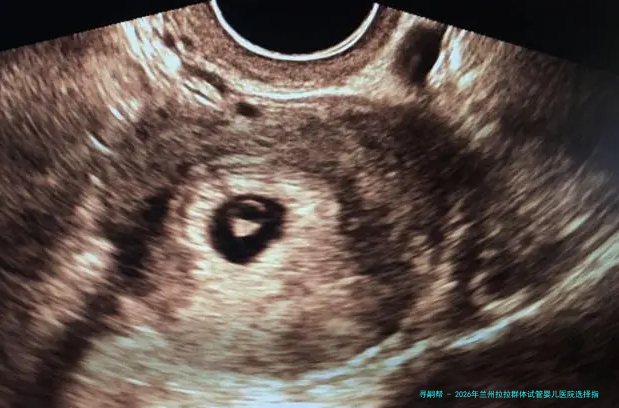

2026年兰州拉拉群体试管婴儿医院选择指南:附本地生殖中心服务特色与医生专长解析

本 文 摘 要 2026年兰州拉拉群体试管婴儿医院选择指南:附本地生殖中心服务特色与医生专长解析,对于兰州的拉拉伴侣而言,选择一家技术过硬、服务贴心且对多元家庭友好的生殖中心,是实现生育梦想的关键一步。这不仅仅是选择一家医院,更是选择一个能理解、尊重并专业支持你们特殊需求的团队。本文将基于本地生殖医学中心的综合实力、服务口碑...

至于兰州的女同伴侣而言,挑选一家技术过硬、服务暖心且对多元家庭和睦的生殖医学中心,是达成生育梦想的关键一步。这不只是选择一家医院,更是选择1个能理解、尊崇并专业支持你们特殊需求的团队。本文将鉴于要地本地辅助生殖医学中心的综合力量、服务口碑及对特殊群体的容纳性,为众人梳理一份详确的选择参考。